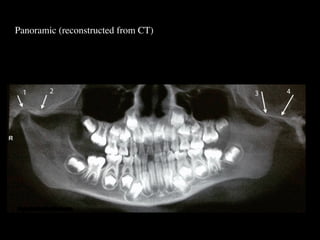

Panoramic (reconstructed from CT)

The most likely diagnosis for the facial asymmetry of this young girl is an

undiagnosed condylar fracture that most likely happen when she falled on a meta

crossbar bar ladder 2 or 3 years ago while she was 4 - 5 years old or so. The

condylar stump has healed and a new condylar head has formed, but the losted

substance of the condyle is gone. Therfore, the height of the ramus has

shortened.

The left ramus and condylar neck are shorter and the left eminence has no slope

if any. Healing and normal growth had reshaped both condyle and eminence.

!

Read more

When looking to the condyle from an anterior view, one can see the oblong

shape of a condyle but the left condyle is smaller.

The midline are not coincident. Note that the lower midline is toward right like

the occlusal plane canting to the right. This can be explained by the lack of

heigh of the left ramus and as normal growth occur, there is a wagon wheel

effect and the midline deviate toward the normal side, the occlusal plane is

moving up on the affected side.